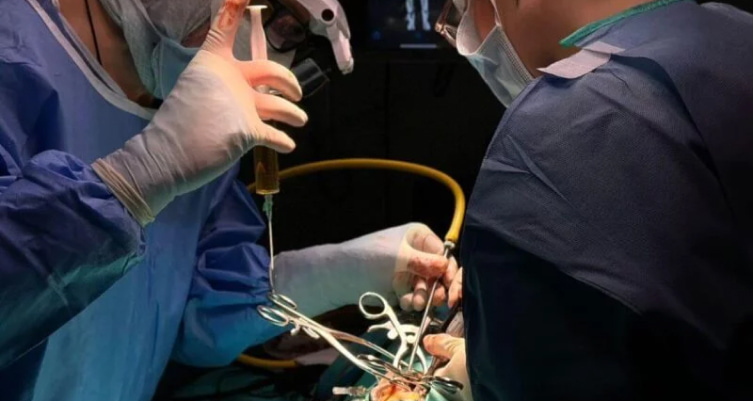

Cirugía avanzada: En casos graves, puede ser necesario